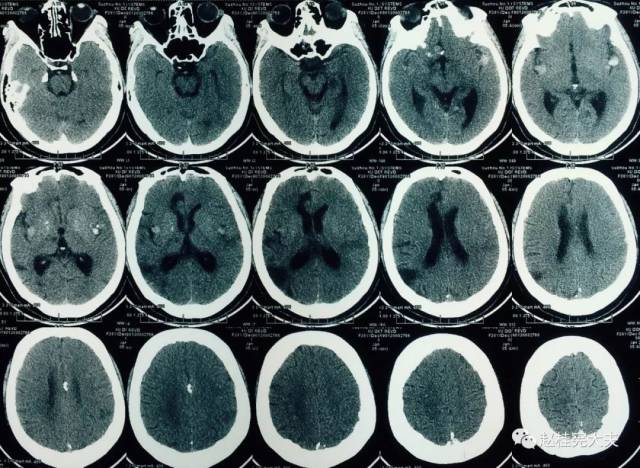

这种病不仅会使脑袋里长石头还会遗传